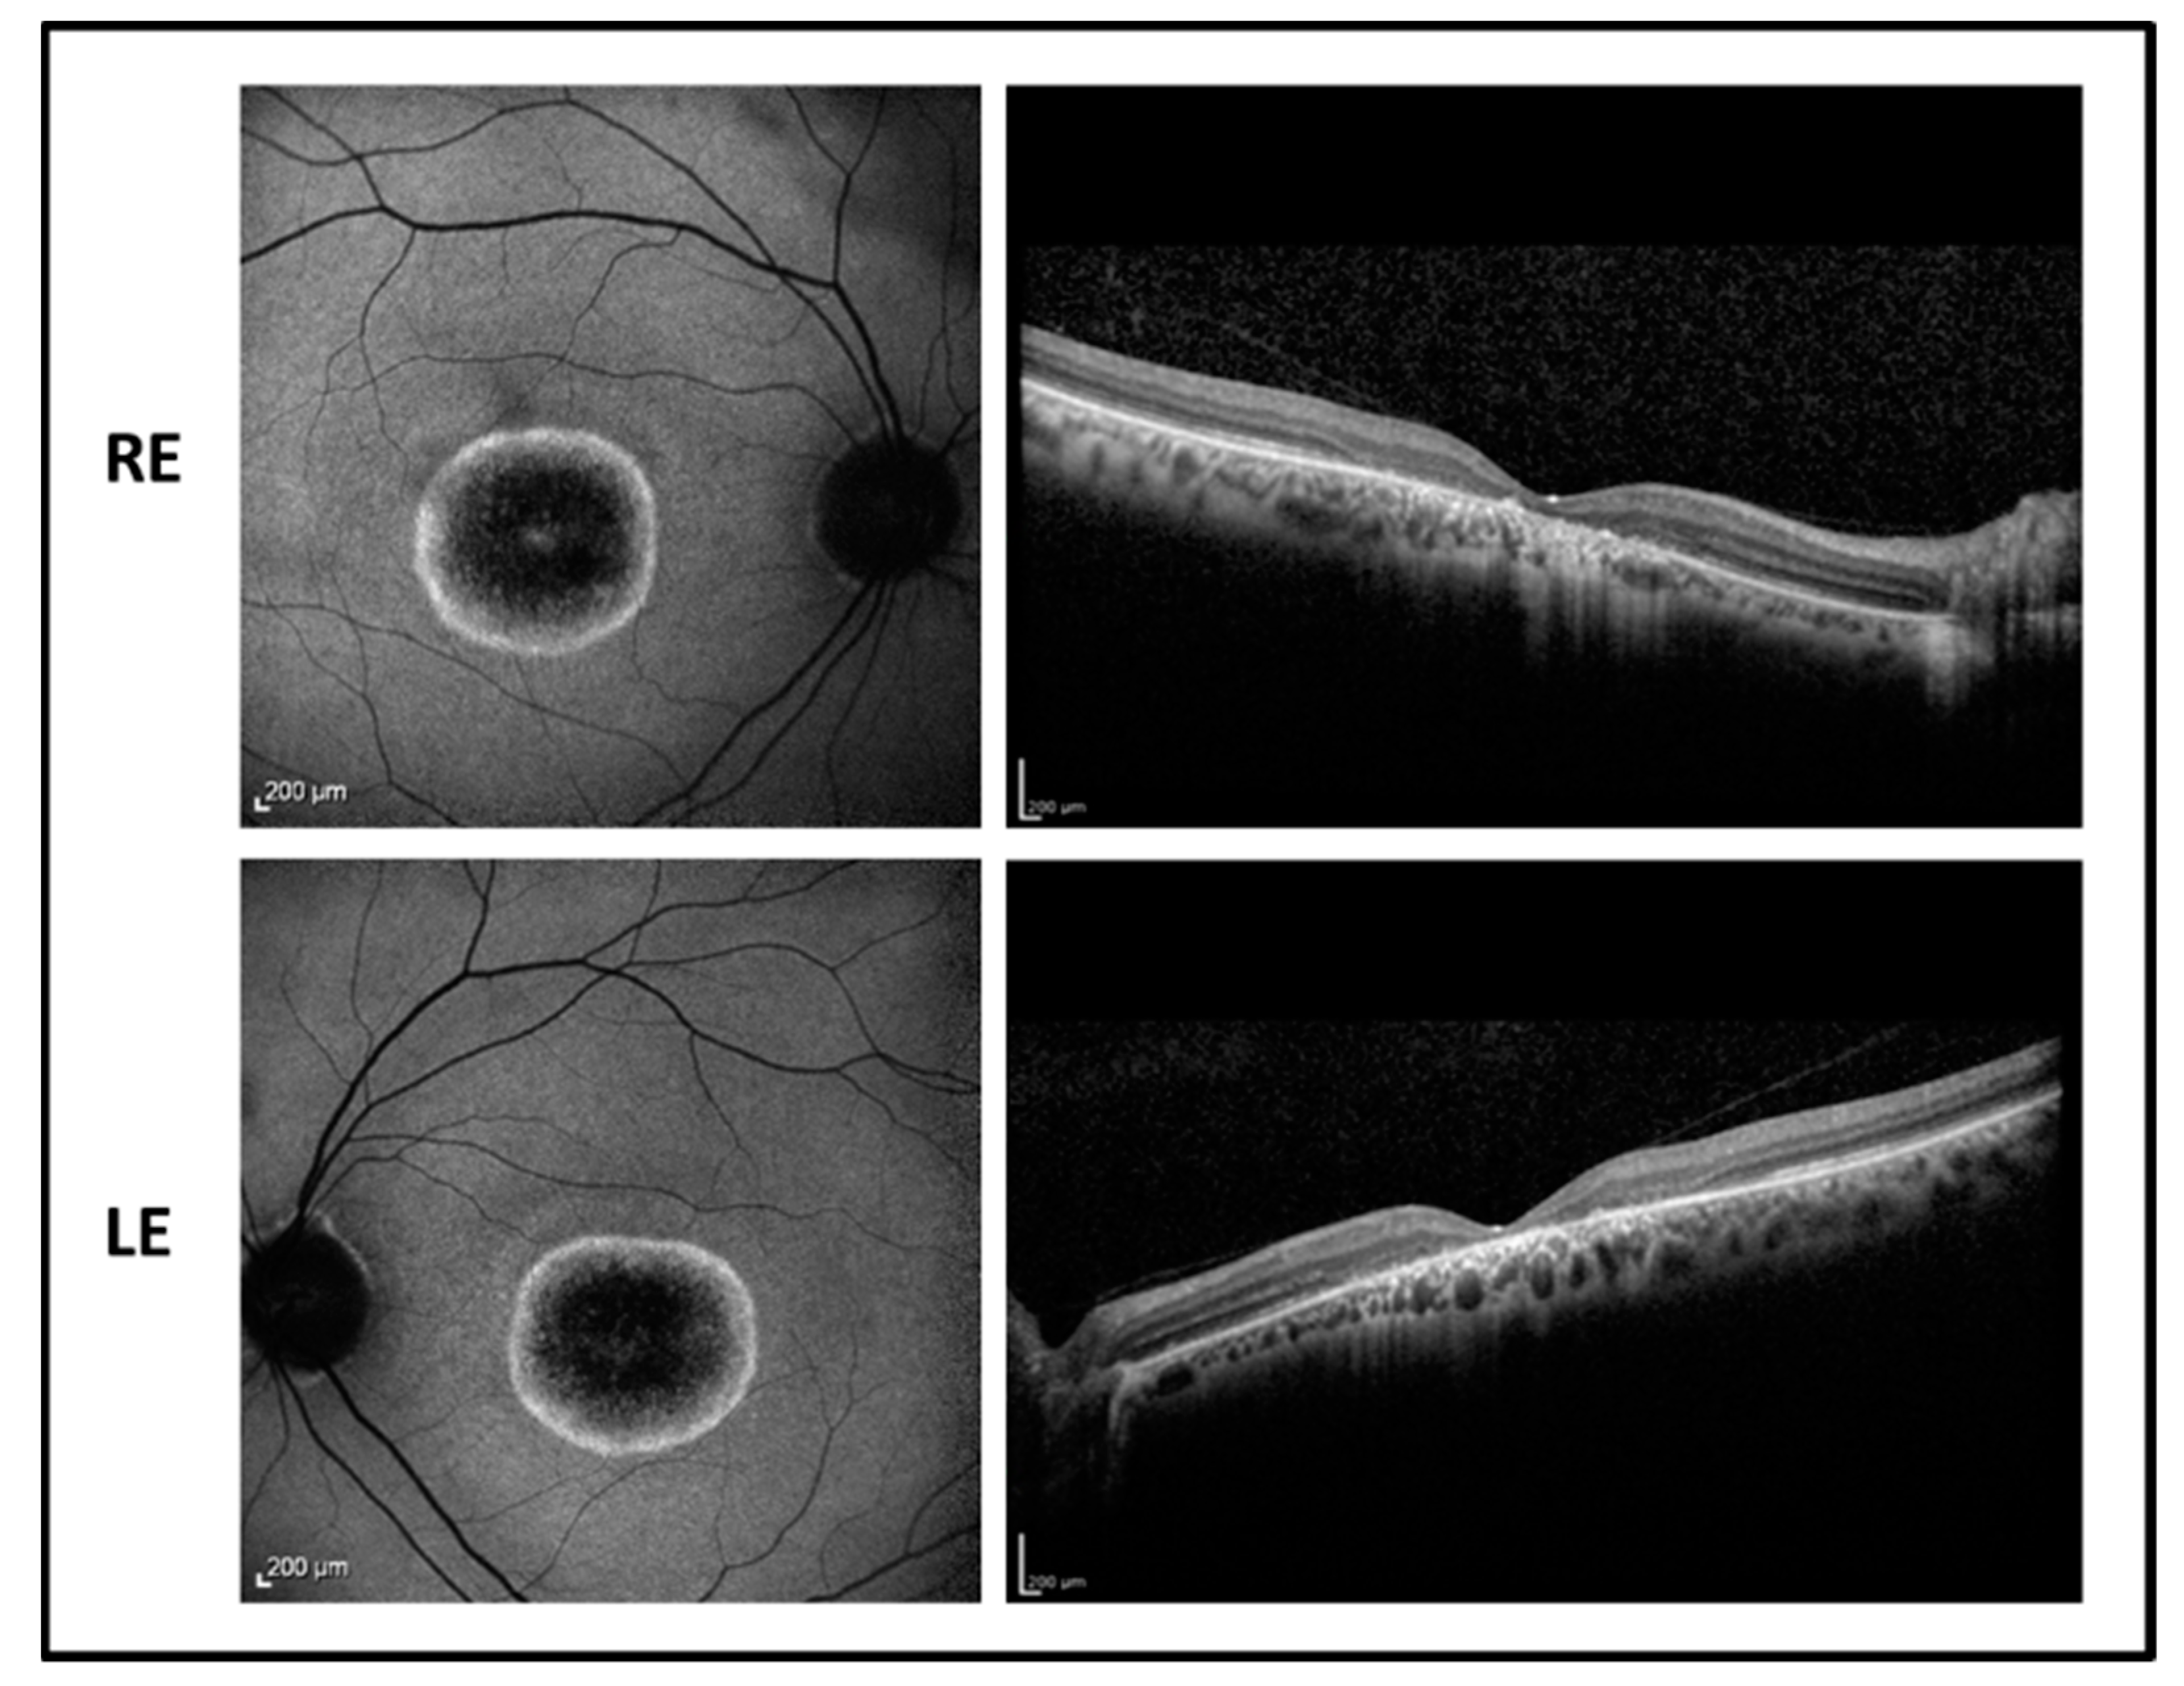

The proband is a 17-year-old boy suffering from poor vision since the age of 10. BCVA was 0.52 LogMAR in both eyes with a refractive error of −5.50 sph −1.00 cyl/100° D in RE and of −5.00 sph −2.00 cyl/65° D in LE. The fundus examination showed normal optic disk, a loss of the foveal reflex, and “salt and pepper” peripheral retinopathy. Fundus autofluorescence (FAF) revealed a central hyperfluorescent area in both eyes while optical coherence tomography (OCT) imaging showed a marked reduction of the foveal thickness associated with a photoreceptor layer disruption (Figure 1).

Figure 1. Fundus autofluorescence (left side) and optical coherence tomography (OCT) (right side) images of the right eye (RE) and left eye (LE) of patient 1 showing macular hyperfluorescence and foveal atrophy with backscattering phenomenon.